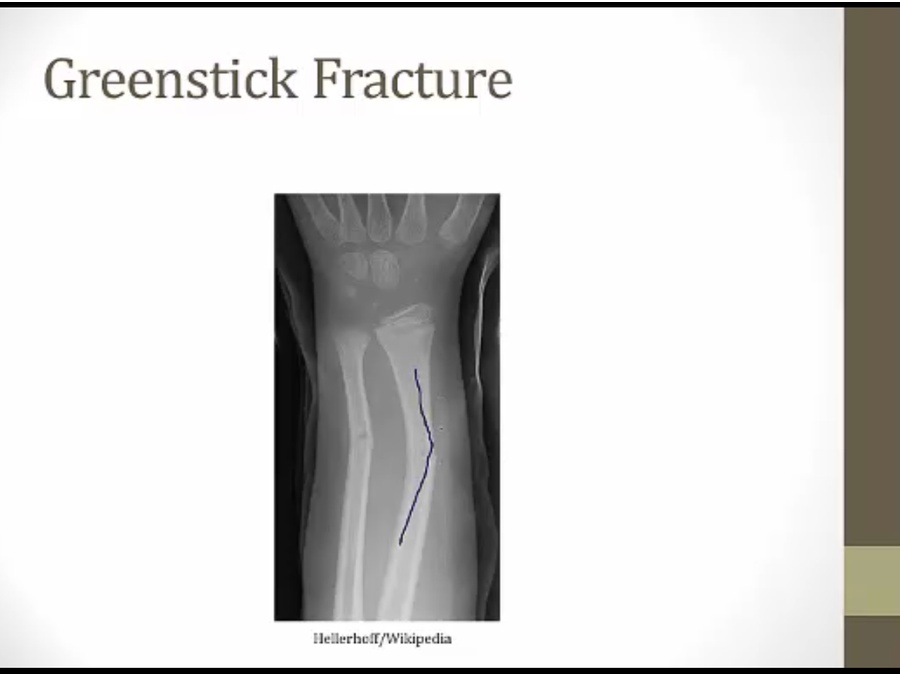

Pediatric

children have softer bones

bone doesn't completely snap in two

Greenstick

part of bone still attached medially